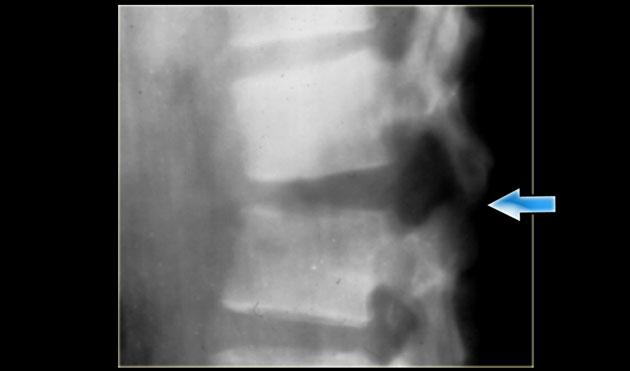

Trên phim X-quang cho thấy tổn thương tăng gấp khúc của L1 với sự tổn thương cột trước và có thể tổn thương cột giữa.

Các tái tạo mặt phẳng đứng dọc trên CT cho thấy phần sau thân đốt sống có chiều cao bình thường, nhưng có một phần tổn thương ở phía sau thân đốt sống.